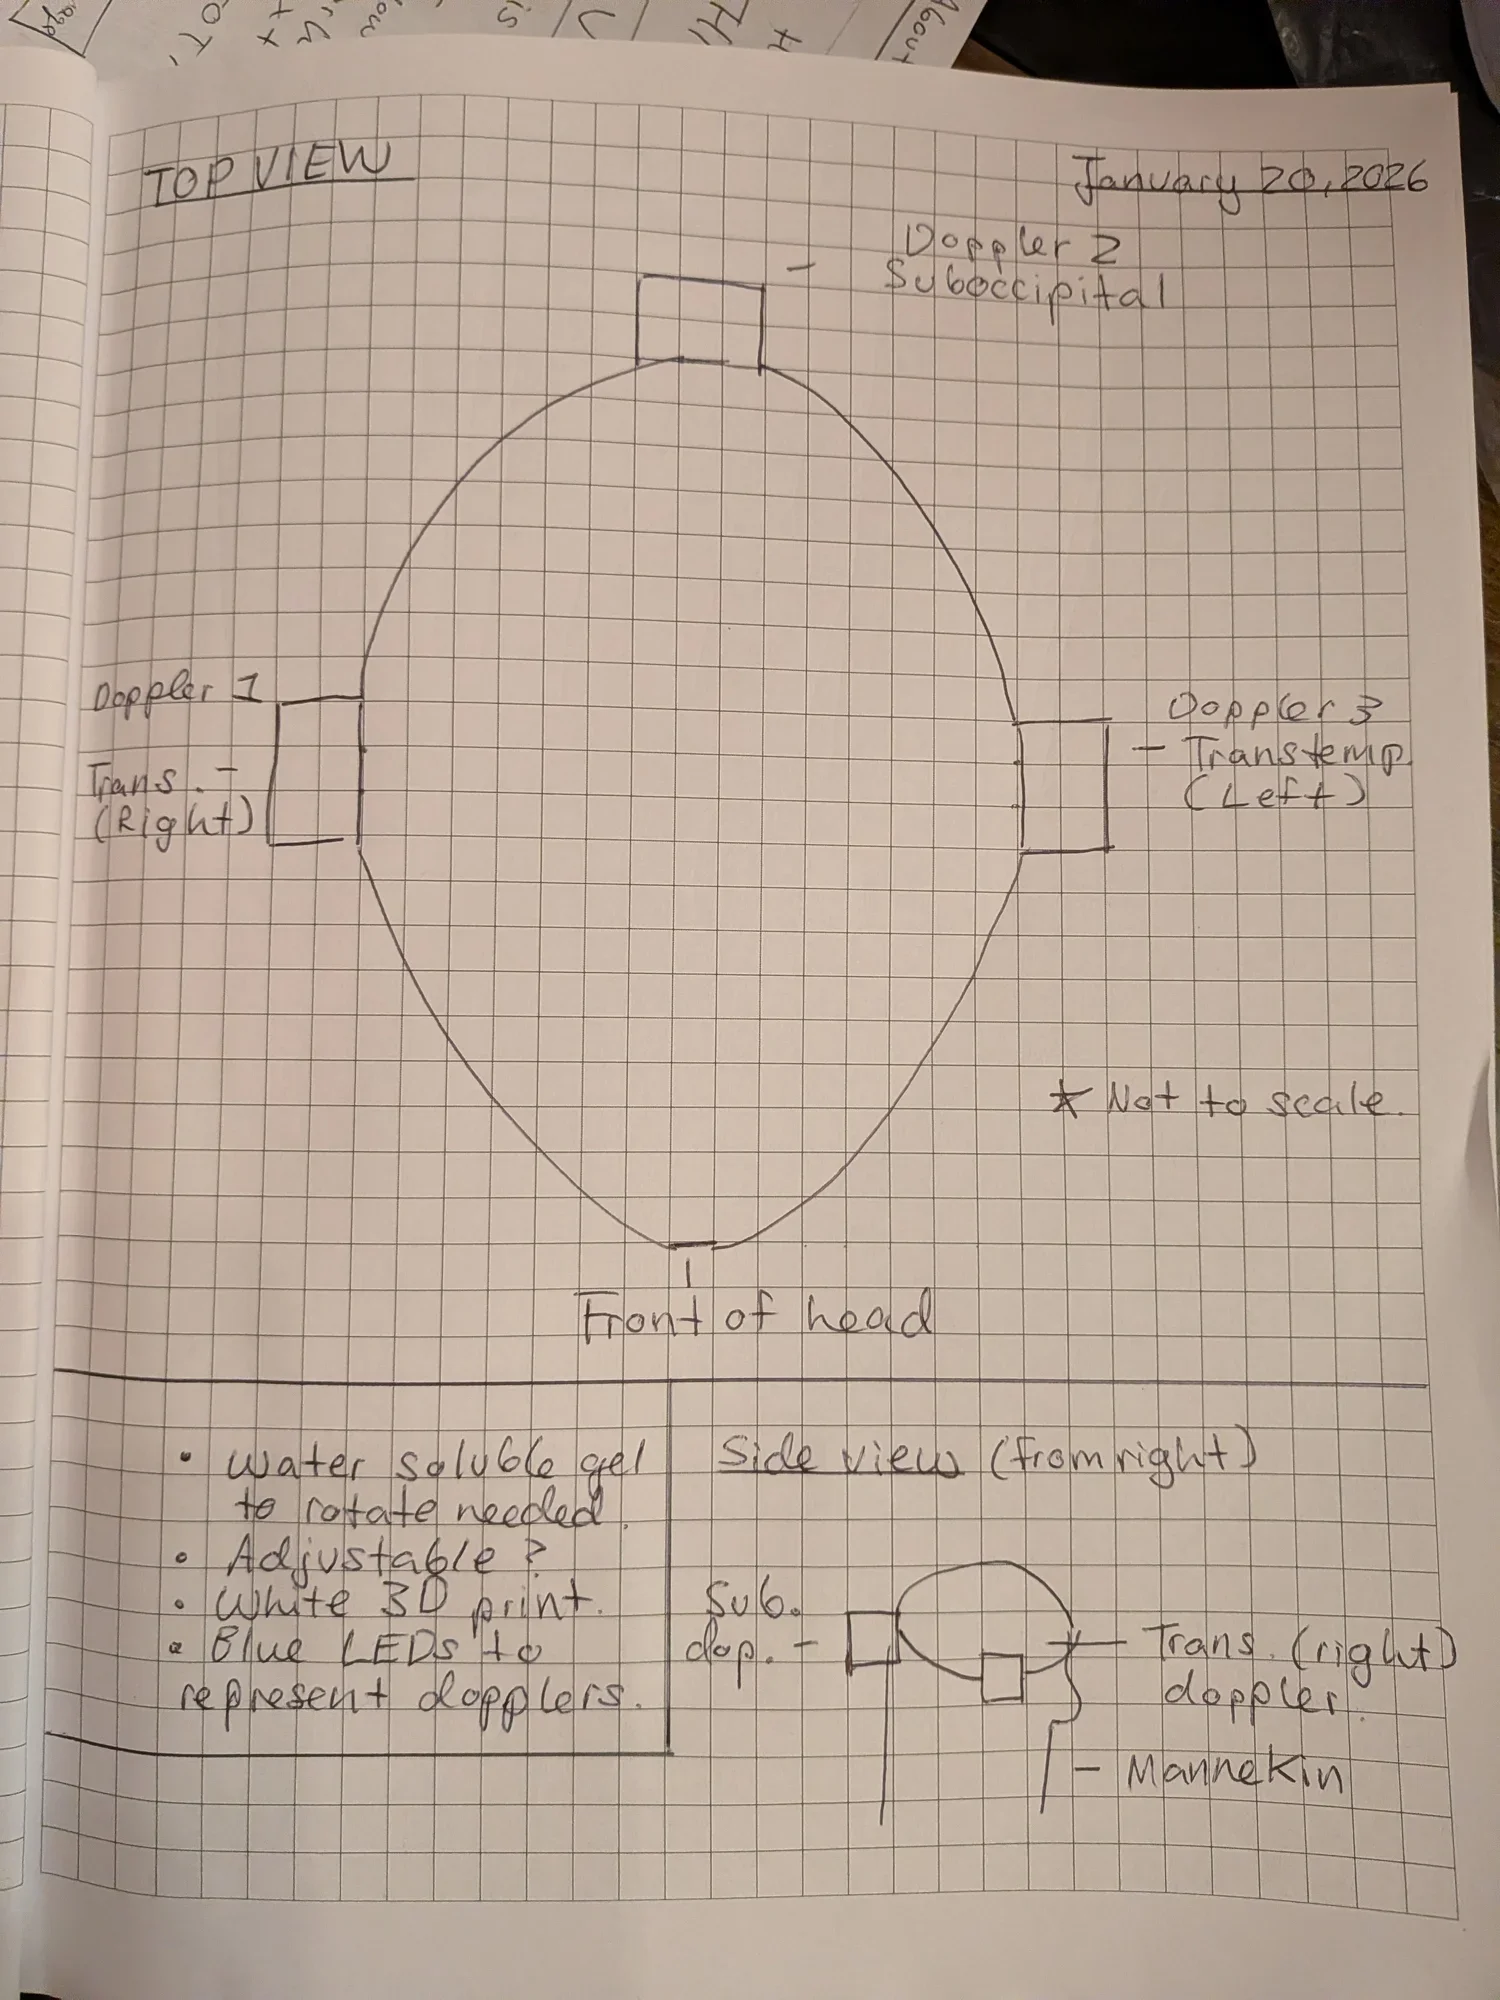

Design

To prove the concept of TONHI, we designed a prototype and wiring setup that will simulate rising intracranial pressure.

Transcranial Dopplers

Transcranial ultrasound dopplers will be placed at both transtemporal lobes and the suboccipital lobe of the patient to capture blood flow information and intracranial pressure.